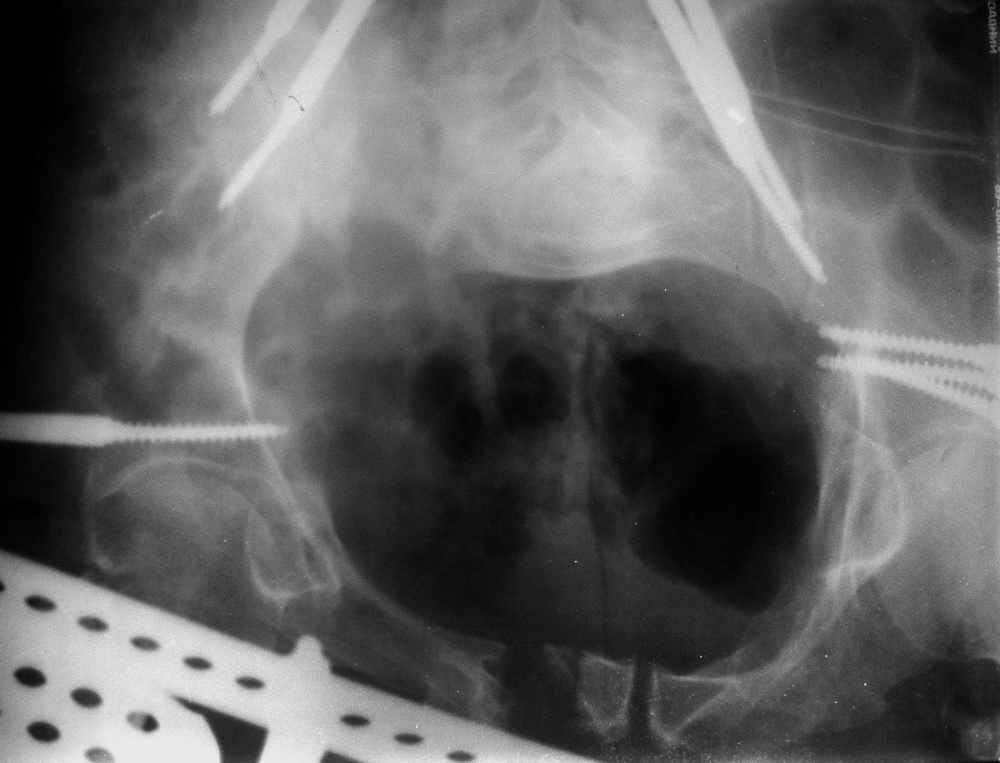

окончательная фиксация